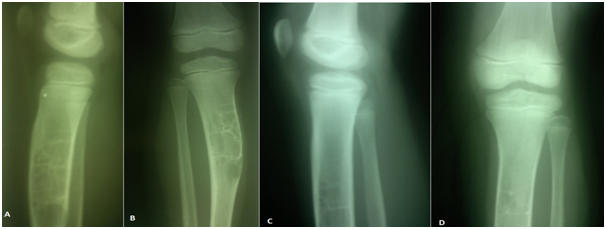

Follow up ranged from 18 months to 4 years for all patients. Close follow up until clinical improvement and radiological consolidation of the cyst. Pain Score according to Healing time ranged from 21 - 90 days with average 42.2 days. Motion of the arm as patients can move their arm without pain was allowed. Weight bearing for the lower limbs also had been allowed as patients felt pain subsided even there is no complete healing radiological. Painless non supported gait was observed and normal full activity with returning to their ordinary activities for all patients. Sports activities like football and running were return to normal in 7 children five out of them had tibial cyst (Figures 2 & 3) and other two patients had proximal femoral cyst (Figures 4 & 5) were returning to their normal sport activities. VAS ranged from 3-9 with average 5.7 which was improved to average 1.5 at final follow up (Figure 6). At final radiological evaluation we found all cases had consolidated felling of cysts by bony tissue in X-ray film and continuity of the cortical osseous structures. No cases of recurrence were observed for the last follow up of all patients.

Figure 3 Follow up X-ray for the girl A,B: 2 years follow up with formed tibia, C,D : 3 years follow up of the patients with remodeling of the tibia and normal consolidated bone.